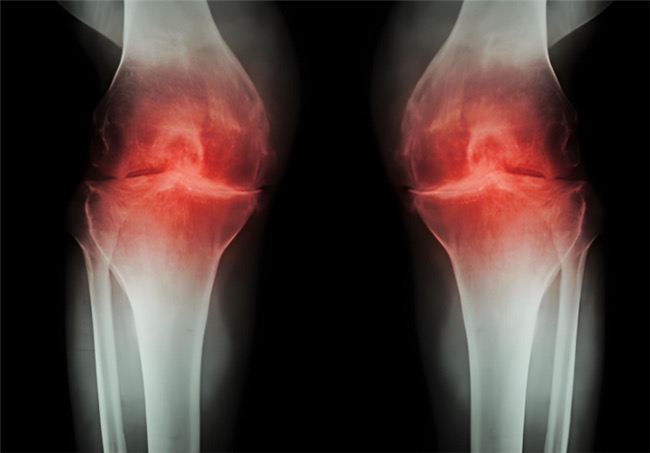

骨关节炎作为常见的关节退行性疾病,困扰着众多中老年人乃至长期劳损的人群。患者不仅会频繁遭遇关节疼痛、肿胀、僵硬等不适,随着病情发展,还可能出现活动受限、关节变形,进而影响走路、上下楼等日常行为,让生活质量大打折扣。更令人担忧的是,骨关节炎的病程一旦进入中晚期,治疗难度和痛苦都会明显增加。因此,及早干预至关重要。而氨基葡萄糖就是临床常用的治疗药物之一,但它还有盐酸和硫酸氨基葡萄糖之分,到底盐酸和硫酸氨基葡萄糖的作用与功效有什么不同?骨关节炎患者如何选择呢?

盐酸和硫酸氨基葡萄糖胶囊都是氨基葡萄糖类药物,能为关节软骨提供合成原料,在促进软骨基质的修复与再生的基础上,补充关节滑液以减少摩擦,同时通过抑制关节腔内的炎症因子,从多个方面帮助延缓骨关节炎的进展[1],但它们在临床疗效上却存在一定差异。